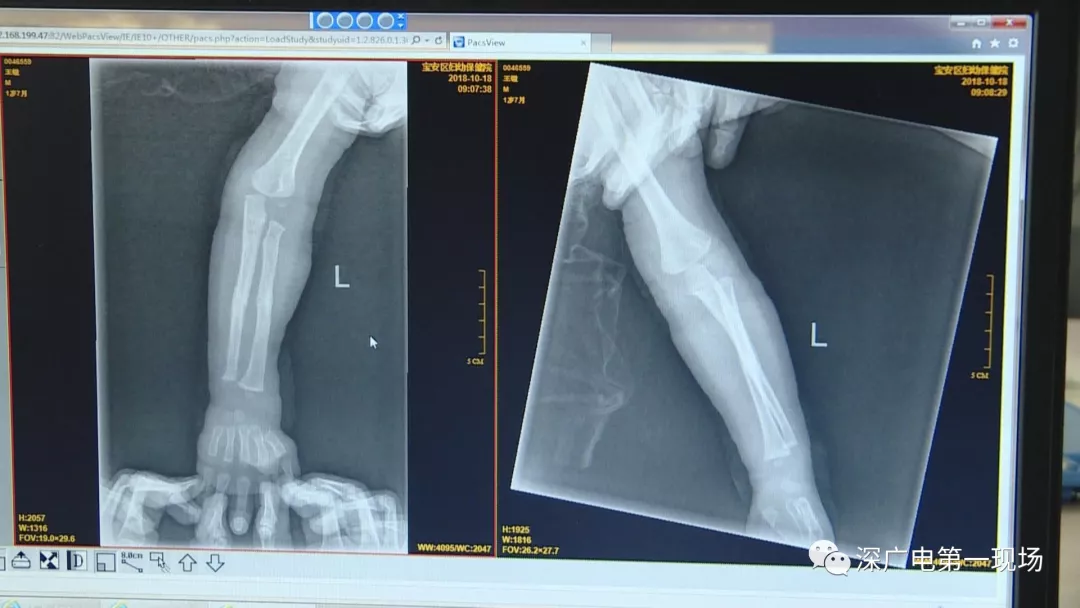

一名1歲多的男嬰摔斷了胳膊

9月4號,一名1歲零5個(gè)月的男嬰因在家中摔傷,被父母送到了寶安區(qū)婦幼保健院,醫(yī)生診斷為左側(cè)尺橈骨骨折。在進(jìn)行全麻手術(shù)之前,院方例行對嬰兒進(jìn)行了周身檢查。手術(shù)前,兒外科醫(yī)生趙冠聰在查看患者的胸片時(shí),發(fā)現(xiàn)這名嬰兒的胃部有一枚硬幣大小的暗影。